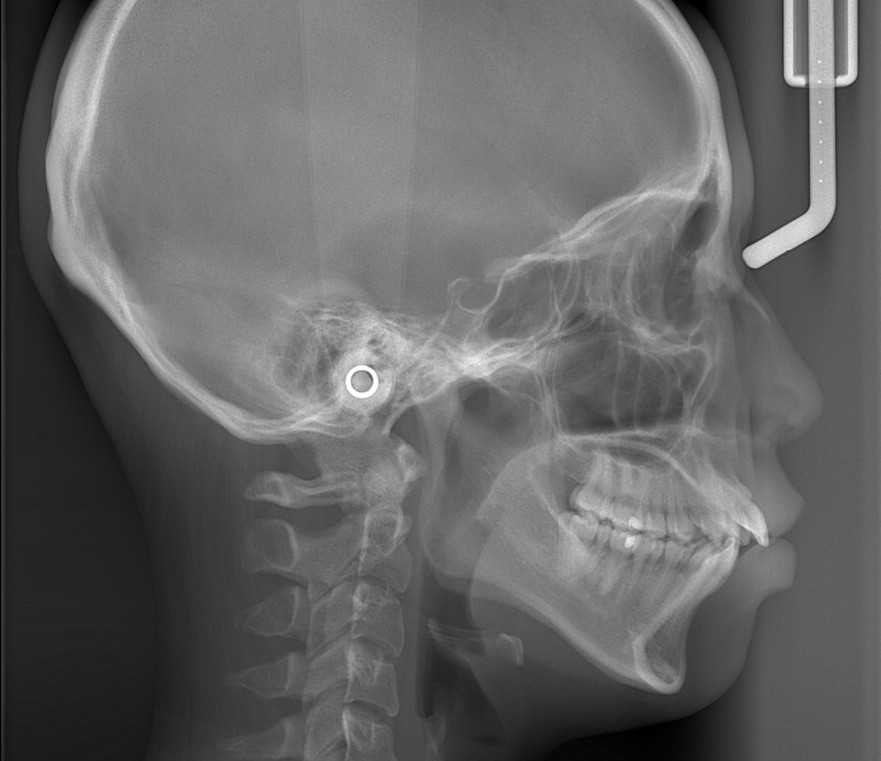

レントゲン写真で確認すると、

この患者さんの場合、

レントゲン写真でも矯正治療前後を比較してみましょう

レントゲンで見ると、治療前後で口元の変化は小さいように見えますが・・・